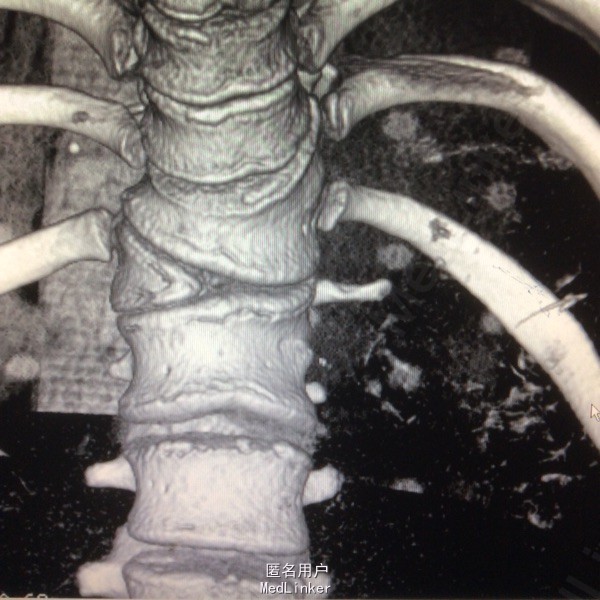

患者呈向心性肥胖,眼角略上斜,下颌小,上下牙间距大,闭齿音发音不清,性早熟,外阴幼稚,大小阴唇发育不良,手脚小胖,指端纤细,余查体无明显异常。 辅助检查:胸9-10胸12-腰1椎体融合、胸11呈半椎体,椎管内脊髓未见明显信号异常.

胸椎半椎体畸形 左侧第10肋骨缺如 隐形骶椎裂 双下肢膝外翻 双下肢肌挛缩症 脊柱畸形术,胸5、6、8、9腰1-2-3双侧椎弓根螺钉,去除胸11-12后方椎板,胸12半椎体及上下间隙间盘去除,椎间隙植骨。